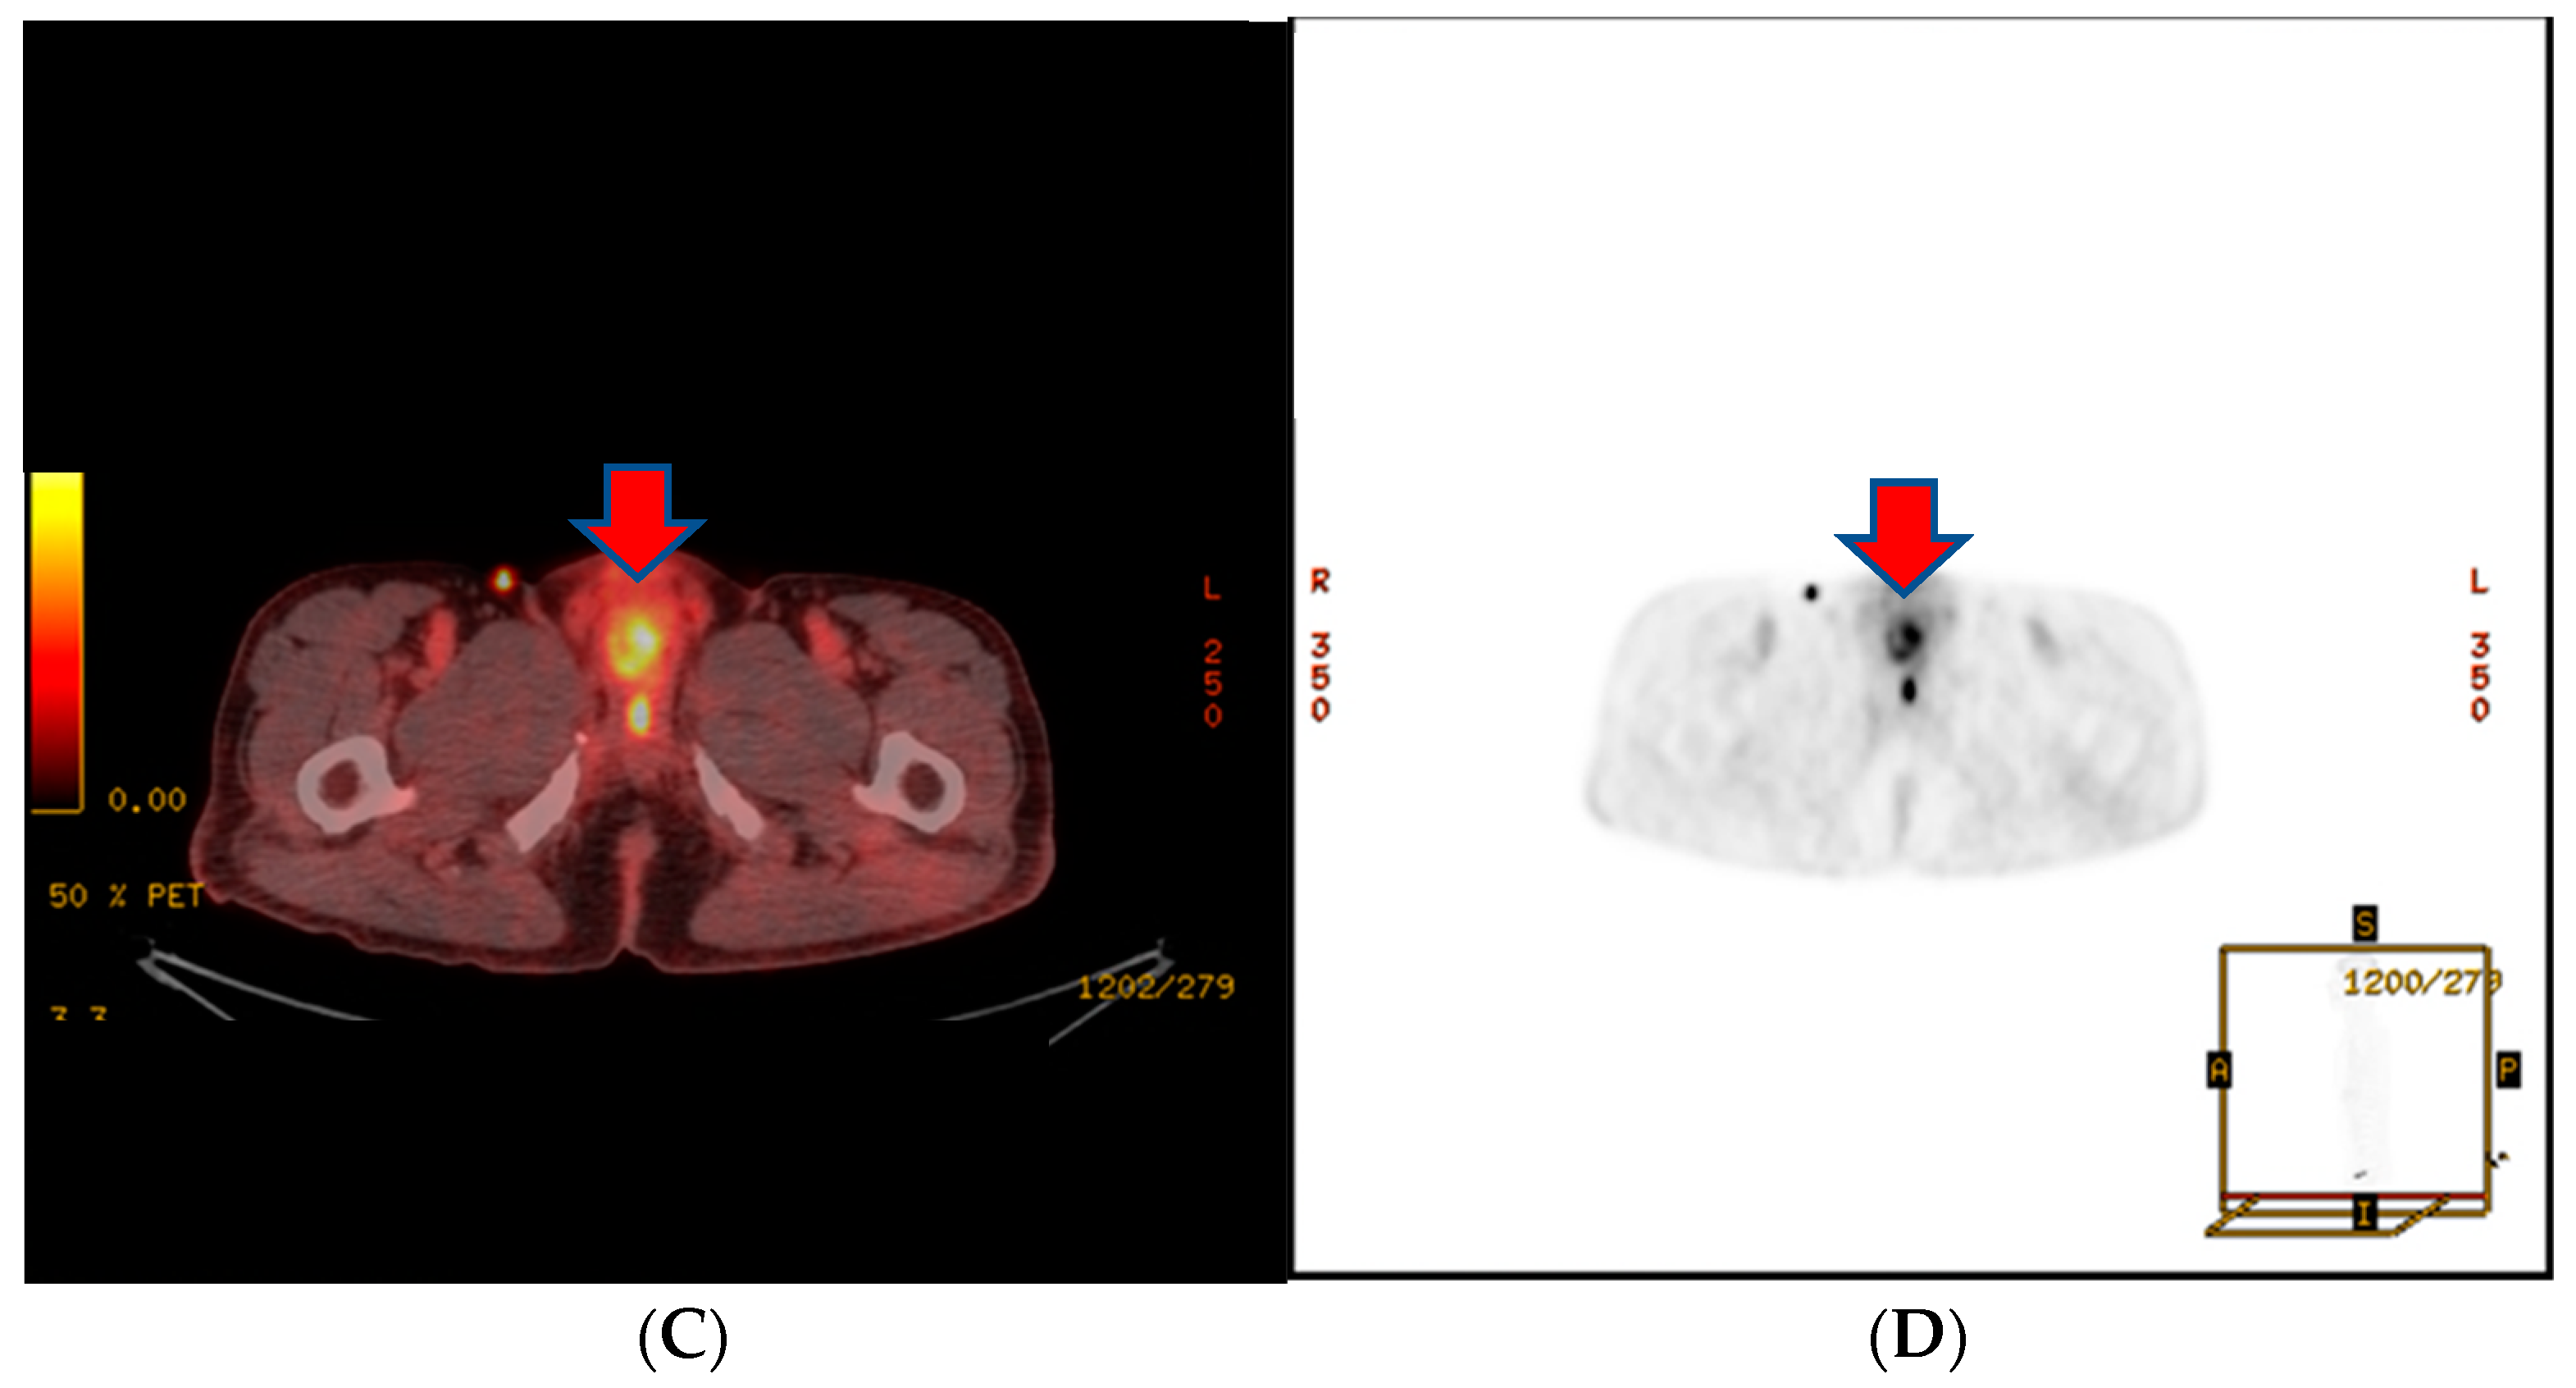

About a month after the surgical procedure, the patient began experiencing penile discomfort, which worsened over three months, prompting his hospital visit. Upon physical examination, a palpable mass was detected at the penoscrotal junction of the penis. The mass was tender, firm in consistency without ulcerations or rash, and measured approximately 5 cm in diameter. No other abnormalities were noted during the examination of the genitalia. Subsequent to this, a CT scan revealed an irregularly shaped enhancing mass in the penis, suggesting the possibility of metastasis (Figure 3). Laboratory results were within normal ranges. On urinalysis, pyuria was observed, but the urine culture showed no microorganism. Magnetic resonance imaging (MRI) findings revealed a lobulated contour and heterogeneously enhanced mass-like lesion in the corpus cavernosa of the penis on T2-weighted images, which raised the possibility of metastasis (Figure 3). A PET-CT showed an irregular increased fludeoxyglucose (FDG) uptake in the penis (Figure 3).

Figure 3.

(A) An irregularly shaped enhancing mass in the penis on CT scan. (B) Magnetic resonance imaging (MRI) findings showing a heterogeneously enhanced mass-like lesion in the corpus cavernosa of the penis on T2-weighted images. (C,D) PET-CT showing an irregular increased fludeoxyglucose (FDG) uptake in the penis.